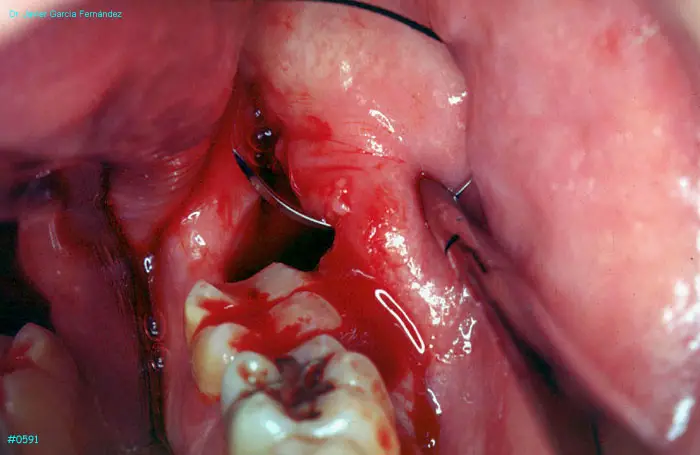

Atlas of Surgical Techniques in Periodontics. Chapter II. Atlas de Técnicas Quirúrgicas en Periodoncia